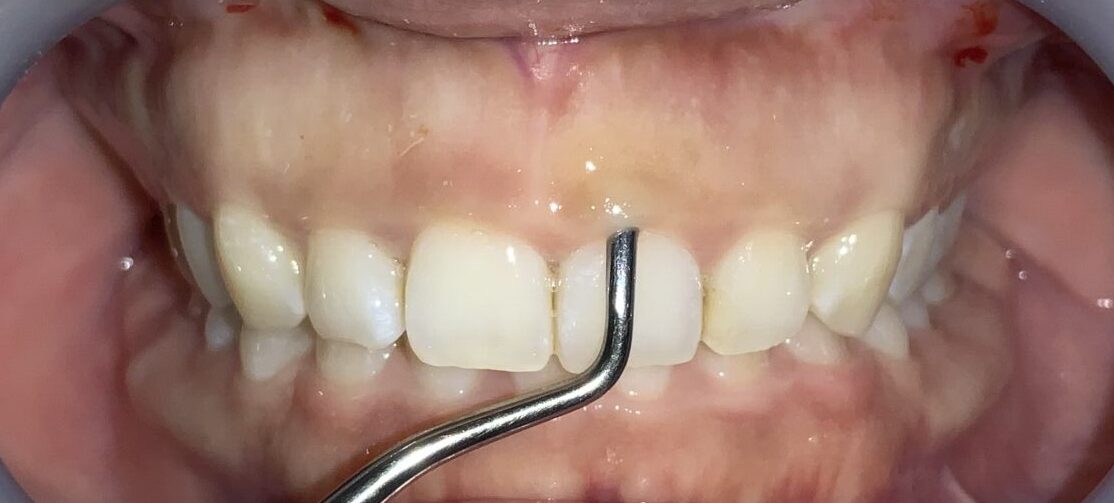

患者様のOKが出たので、すべての歯の治療を行いました。

歯ぐきの面積が少なくなって、笑った時の歯ぐきが見えなくなり、歯の形も、歯ぐきの形も綺麗に改善しました。

歯ぐきが一部黒ずんでいる部分は、数日で改善するのでご安心ください。